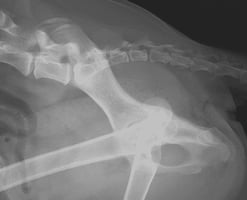

What’s hip in orthopaedics? Unilateral total hip replacement in a dog

Canine hip dysplasia (HD) is a common problem in dogs, affecting mostly larger breeds where the coxo...

17 min read